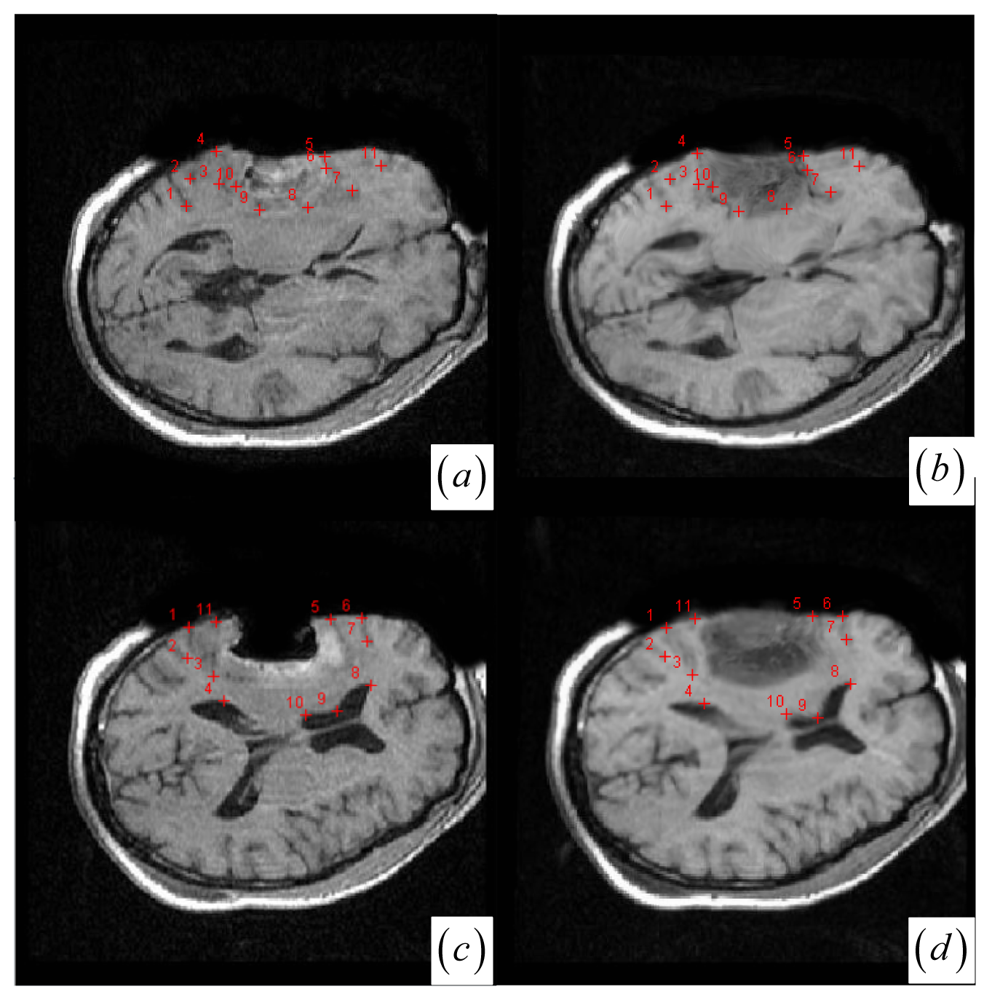

Note that if one cluster pair of tumor regions suffers from the large structural mismatches with local large deformation and outliers, this cluster pair will bring together many keypoints and small average JSM value ζk (computed as ζk = Σw (yi)/card (Ck) (yiCk)). Therefore, the keypoint cluster of tumor region in each image can be localized if its ζk is below a threshold value (ζthreshold = 0.4). In Figure 1j and Figure 2a,b, the keypoint clusters in both images are sorted according to the average JSM values {0.266, 0.404, 0.494, 0.533, 0.560, 0.565, 0.590, 0.639, 0.734}. The tumor resection clusters with ζ1 = 0.266 could be automatically detected from the nine clusters. Figure 2e,f shows that the two images have ten clusters with the tumor resection cluster having 0.234 average JSM value. Furthermore, the keypoint clusters of tumor regions in both images could be regarded as an ellipse model based on the mean and variation of the cluster, and then the outlier keypoints inside the ellipse are removed while the boundary significant keypoints (Figure 2c,d,g,h) are saved for subsequent correspondence detection, i.e., delete x = (x, y) if [ (xμx)2/(κσx)2 + (yμy)2/(κσy)2] < 1 with κ = 0.1. After outlier keypoint rejection, we approach the control point setup and related correspondence detection as follows.

• Choose the significant keypoints for irregular control point setup. The SIFT keypoint detector has assigned a location and a scale to each stable DoG keypoint. The scale defines the saliency measure of each keypoint such that the keypoint with a large scale could be identified at the same location in the noisy pre- and intra-operative MR brain images. Based on the above consideration, a keypoint with the largest scale measure within a neighborhood could be saved as the significant keypoint in a cluster. In Figure 2a,b,e,f, the significant keypoints selected from each cluster well represent the irregular control point setup in the salient structures. Figure 2c,d,g,h shows the boundary significant keypoints at the tumor resection clusters.

Figure 2. (a)–(b) and (e)–(f) Clustered significant keypoints in the two images. (c)–(d) and (g)–(h) Boundary significant keypoints around tumor resection regions with circles defining the scale measures of the points.